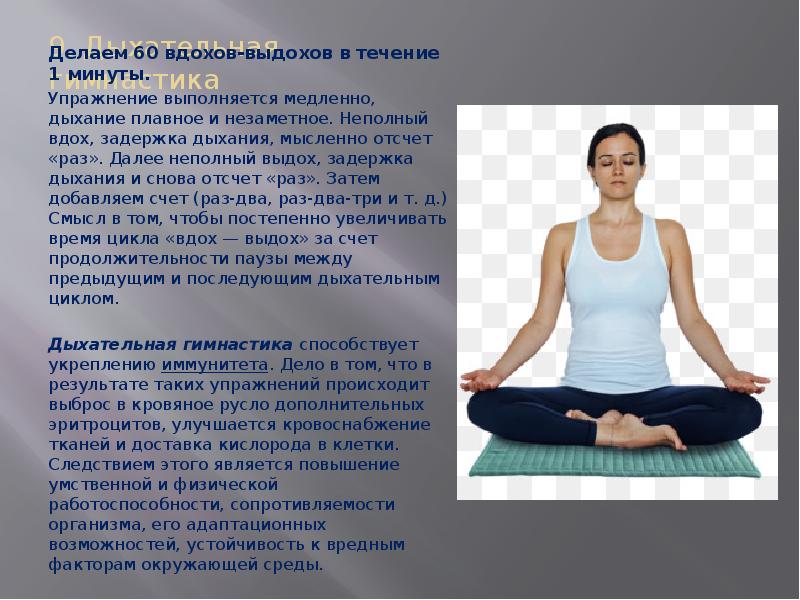

Дыхательная гимнастика при пневмосклерозе: техника и советы